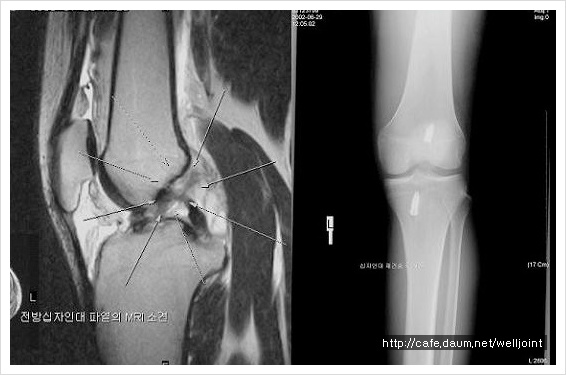

<십자인대파열 --무릎관절내시경수술 전후 MRI와 x-ray >

무릎 관절내시경 수술은 무릎 반월상 연골판손상,십자인대 파열,박리성연골염,추벽증후군,퇴행성관절염,활액막염등의

질환이 있을때 시술하게 됩니다.